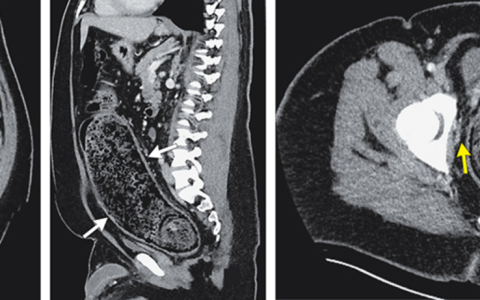

急性主动脉瓣关闭不全,无论是瓣周的还是中央的,都是经导管主动脉瓣置换术 (TAVR) 的已知并发症,据报道发生率高达70%。急性主动脉瓣返流导致收缩期左心室 (LV) 突然容量超负荷。因此,LV收缩末期容积高于正常,在随后的舒张期,左心房和 LV 之间的压力梯度降低较早。这导致早期二尖瓣关闭,可闻及软 S1 音。由于 LV 的心室-动脉梯度变化,观察到早期收缩甚至舒张二尖瓣返流。这导致 LV 每搏输出量减少和反射性心动过速。因此,患者常有脉搏细弱和四肢冰冷。

TAVR 术后曾观察到心包填塞,但较为罕见。此外,据报告,患者的颈静脉搏动在胸骨角上方 5 cm 处,再充盈缓慢,与填塞不一致。败血症与心动过速和低血压相关,但通常与四肢冰冷和体温正常无关。在 TAVR 术后报告了急性三度心脏传导阻滞,但通常与心率过快无关。房室传导完全丧失可引起心输出量下降和低血压,但通常心输出量减少的原因是心动过缓,而不是每搏输出量减少。此外,通常不会观察到舒张期杂音。升主动脉夹层是一种罕见但已知的并发症,肯定比主动脉瓣关闭不全少见。但这应伴有冠状动脉缺血。与急性二尖瓣反流相关的典型杂音是高调、吹风样全收缩期杂音。